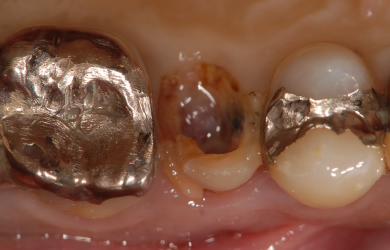

| 主訴 | 右上奥歯を現在、他の歯科医院にて治療中。歯が割れているとのことで抜歯すると言われたので、何か良い方法がないか相談したい。 | ||||||||||||||||||||||||||||||||

| 治療方針 | 初期固定に必要な骨の量がほとんどないため、ソケットリフト法を併用した抜歯即日スピードインプラントを行ってみるが、初期固定がとれなかった場合には通常の段階的な方法にてまず抜歯を行い、その後4カ月ほど待ち、骨が出来てからインプラント手術を行う。 | ||||||||||||||||||||||||||||||||

| 治療内容 | インプラント1本(抜歯即日スピードインプラント+ソケットリフト)、ハイブリッドセラミック1本、メタルボンドセラミック2本、ハイブリッドセラミックインレー1本 | ||||||||||||||||||||||||||||||||